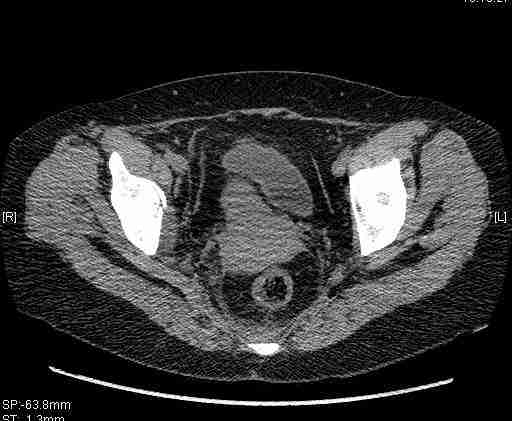

[Ortho] [1/2] Re: Т-образный перелом вертлужной впадины

Удалось сегодня вывести пациентку в соседнюю больницу, где есть кт.

Срезы сделаны  только горизонтальные.